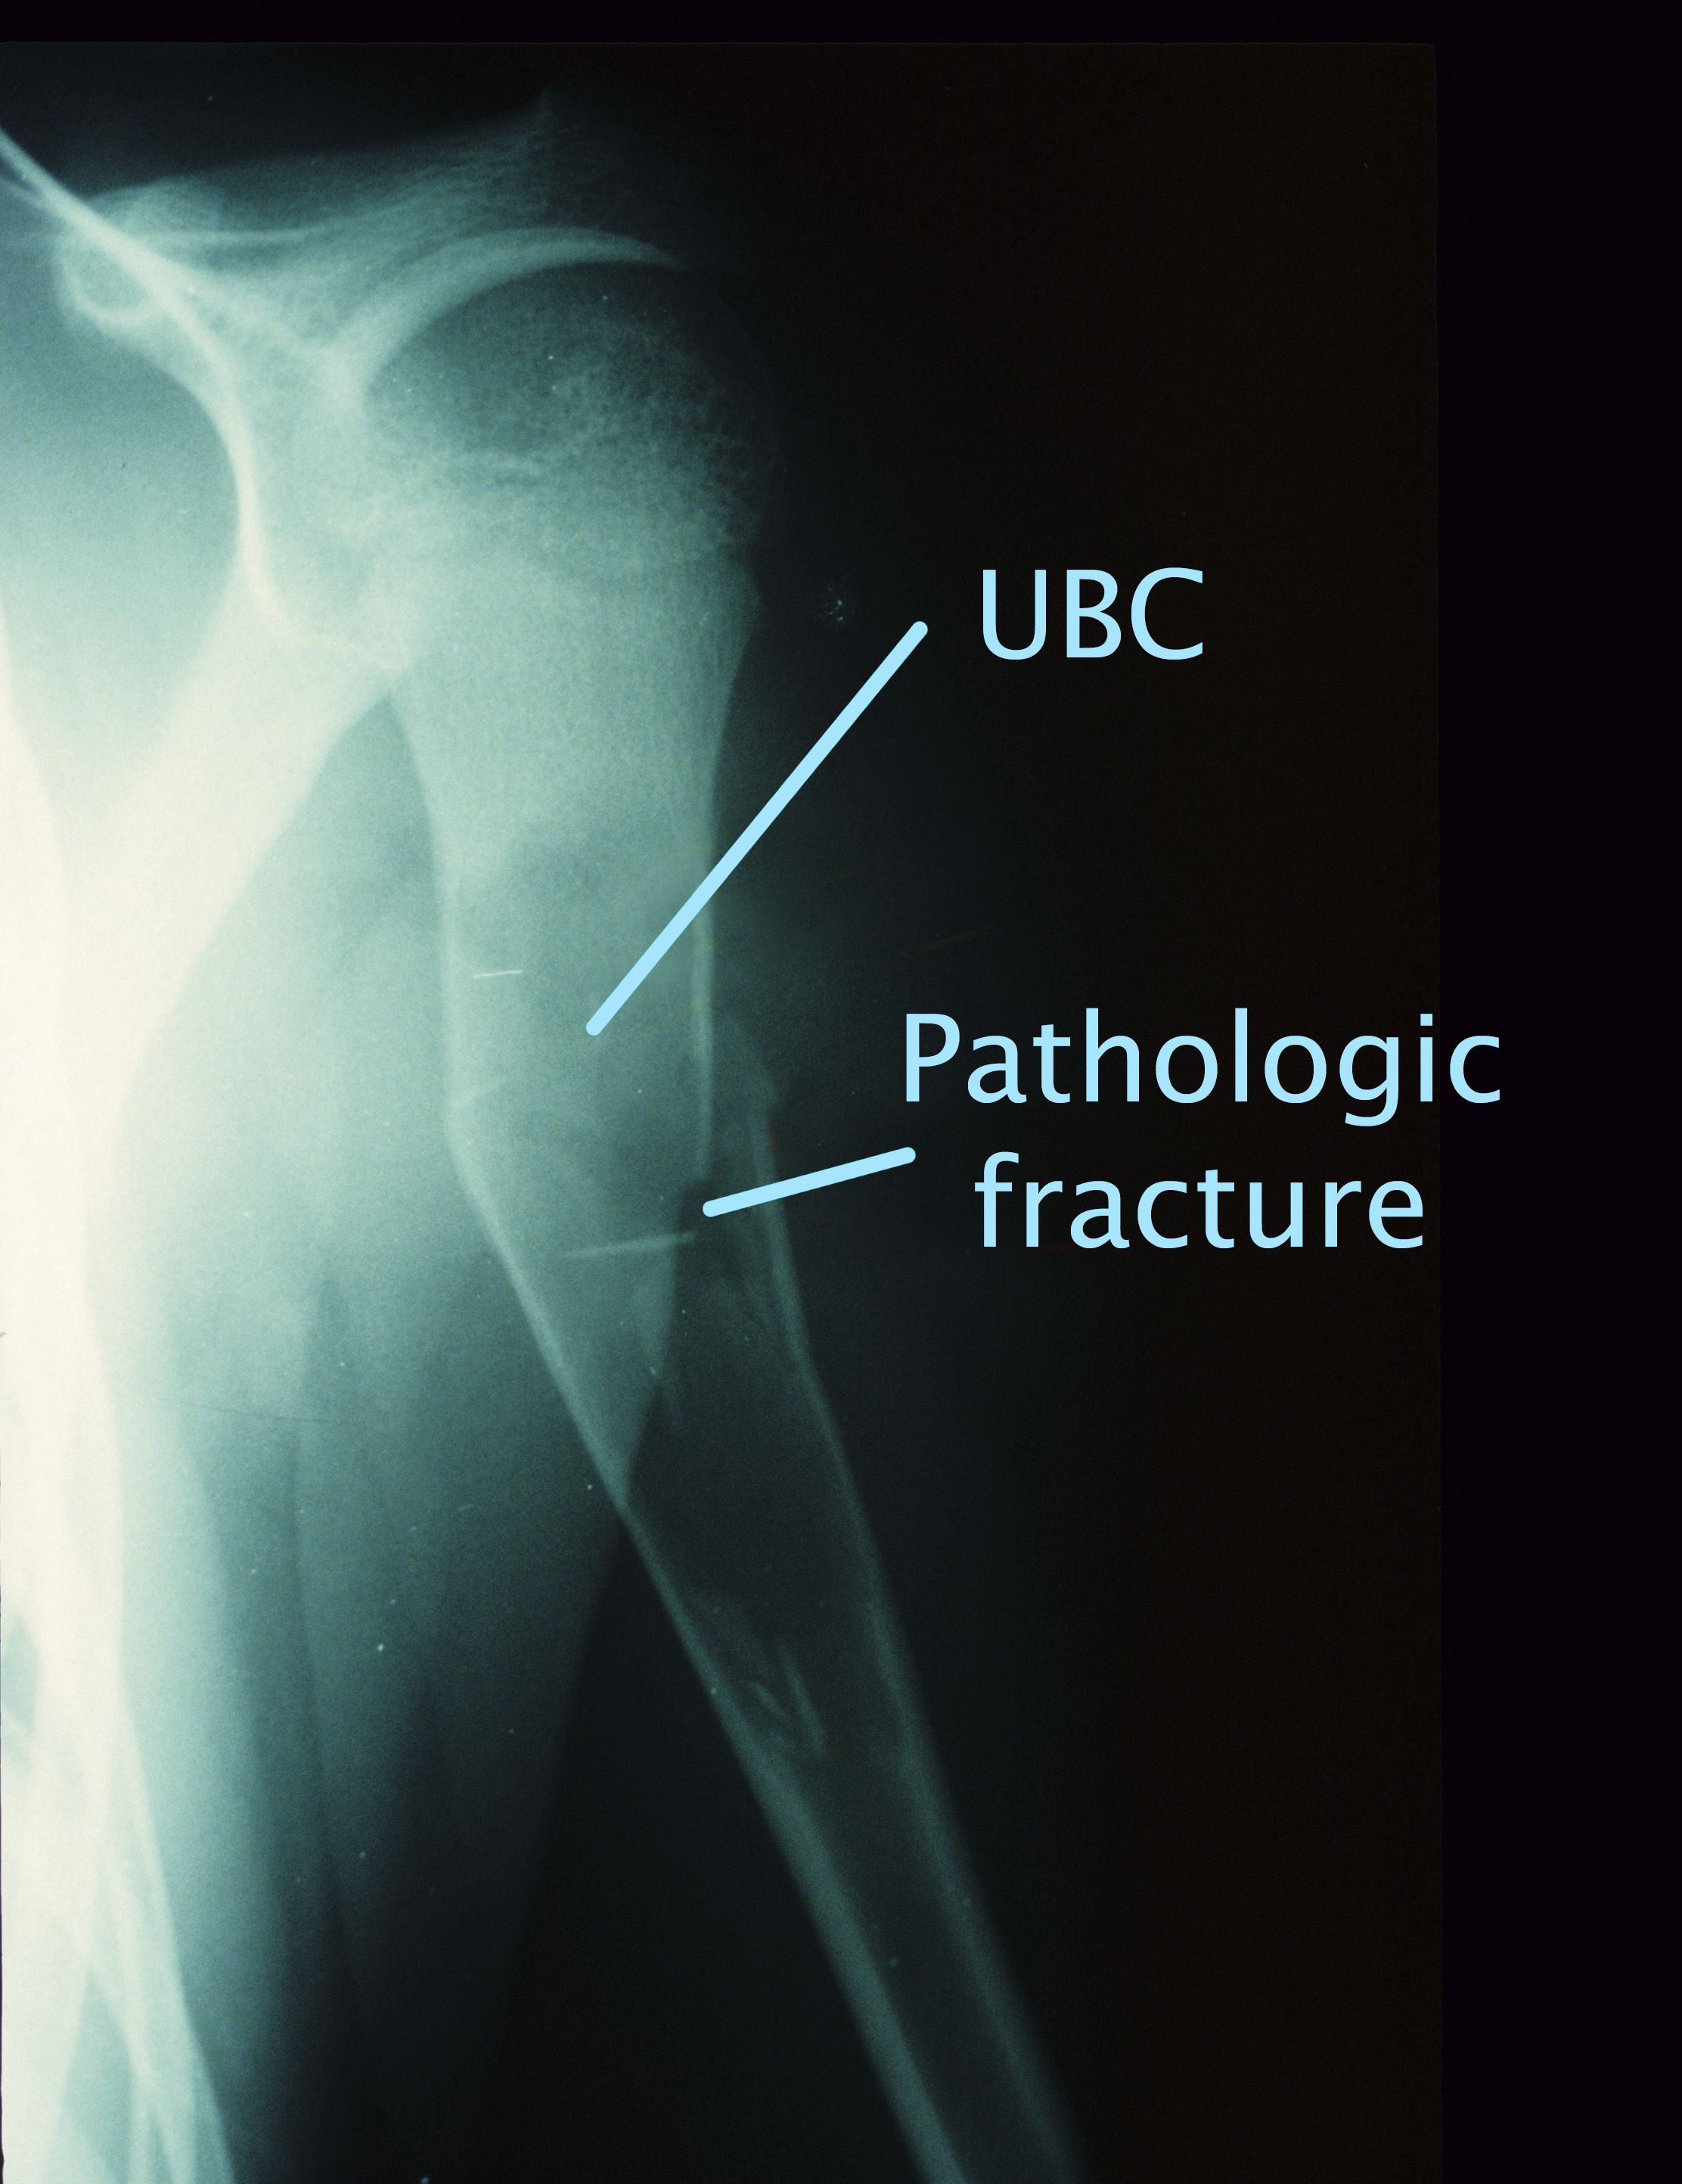

Unicameral bone cyst and pathologic fracture

This X-ray shows a UBC and a pathologic fracture in the humerus (upper arm bone).